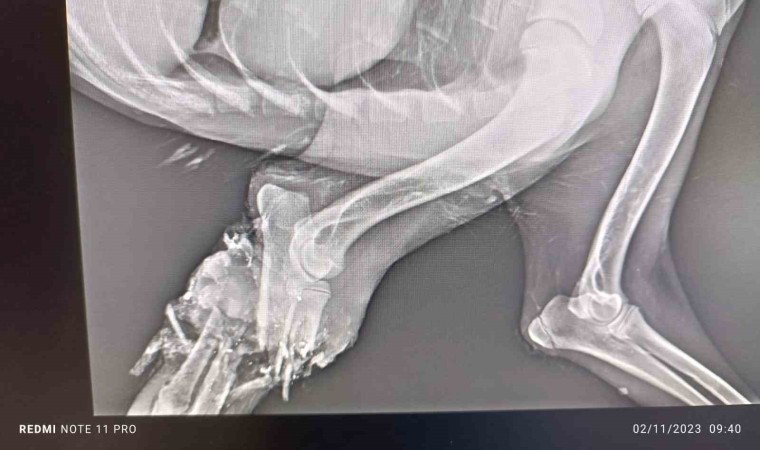

Geçitli köyünden duyarlı bir hayvan sever tarafından Hakkari Belediyesi Veteriner Kliniğine getirilen sahipsiz köpek için veteriner ekipleri harekete geçti. Burada yapılan radyolojik görüntüleme ve inspeksiyon muayenesinde muhtemelen araç çarpması sonucu sağ ön ayağında tam kırık ve kırığın eski olması hesabıyla ayağın kopma noktasına geldiği tespit edildi. Aynı zamanda kangrenleşme söz konusu olduğundan teknik personel ampütasyon ameliyatına karar verildi. 1,5 saat süren ameliyatın ardından başarılı bir ampütasyon operasyon ile can dost kurtarıldı. Veteriner kliniğinde gözlem altına alınan can dostun iyileşmesi ile birlikte doğal yaşam alanına geri bırakılacağı belirtildi.